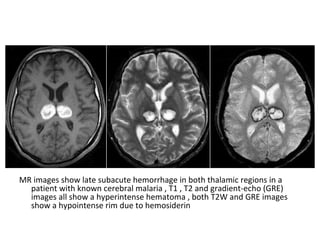

Thrombosis of deep cerebral veins

-The clinical presentation of thrombosis of the

deep cerebral venous system are severe

dysfunction of the diencephalon reflected by

coma and disturbances of eye movements and

pupillary reflexes , usually this results in a

poor outcome

-However , partial syndromes without a decrease in

the level of consciousness or brainstem signs

exist which may lead to initial misdiagnoses

-Deep cerebral venous system thrombosis is an

underdiagnosed condition when symptoms are

mild and should be suspected if the patient is a

young woman , if the lesions are within the basal

ganglia or thalamus and especially if they are

bilateral

Patient with deep cerebral vein thrombosis , notice the bilateral infarctions in

the basal ganglia